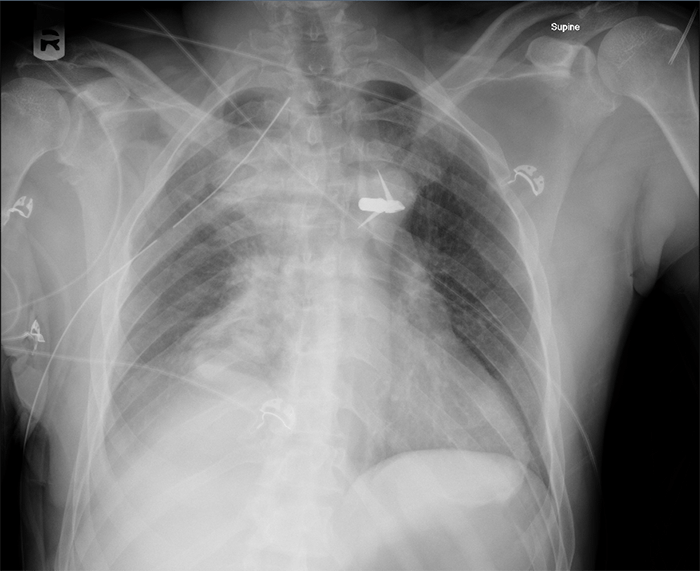

On postoperative day 1, the patient underwent a re-exploration of the right thoracic cavity, with removal of the packs and wound closure. No further evidence of bleeding was observed intra-operatively. A post-operative CT scan showed a T5 vertebral body fracture and T6 superior articular facet fracture (Figure 5). MRI demonstrated partial transection and contusion at T5 (Figure 6). The patient remained in the ICU for 9 days post-operatively. He had continued bilateral lower extremity paralysis below level T4. He was subsequently discharged to inpatient neurologic rehabilitation on post-operative day 11. At the time of discharge, the patient had permanent paraplegia below T3. The patient was seen in clinic seven months after his injury with no further neurologic recovery.

Figure 5. CT thoracic spine without contrast: axial view